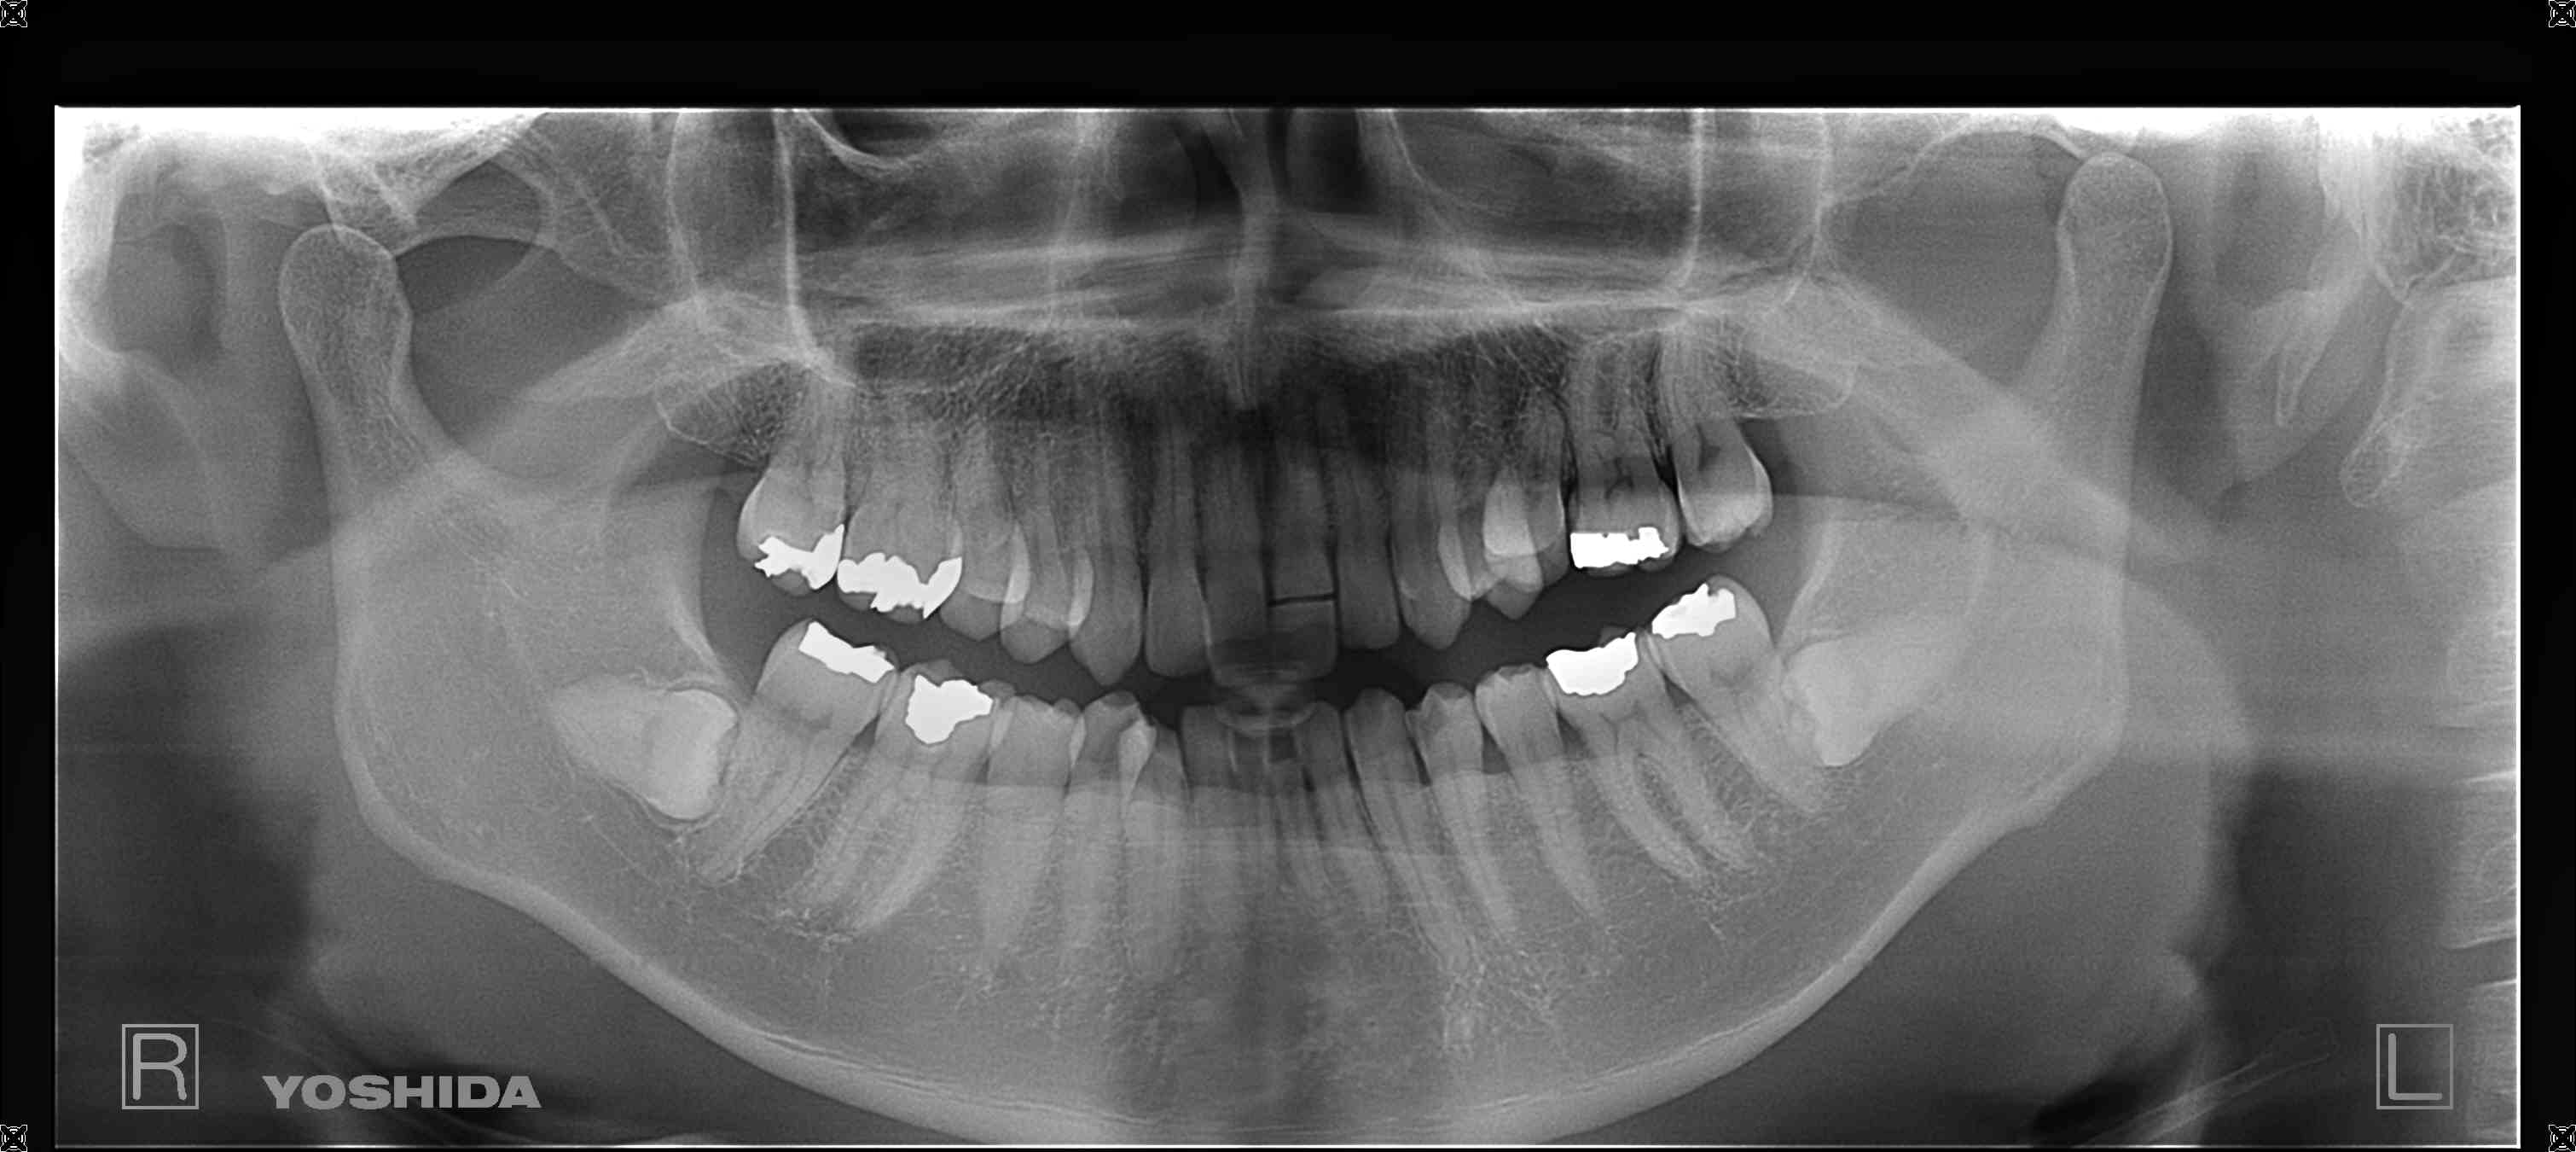

上記写真は、治療前の状態です。